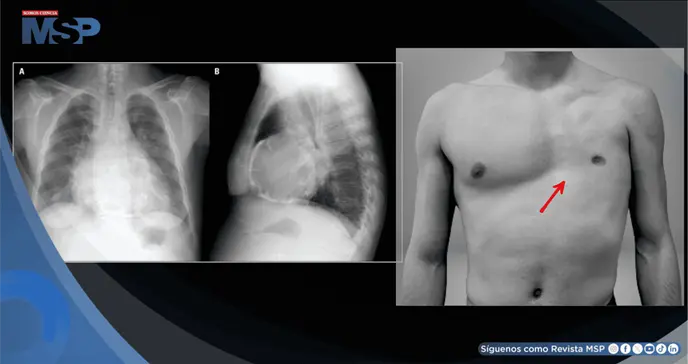

La tomografía de tórax mostró la ausencia completa de los músculos pectorales del lado izquierdo, confirmando por primera vez en la vida del paciente el diagnóstico de síndrome de Poland.

El estudio por imágenes fue fundamental. Una tomografía computarizada (TC) de tórax con contraste descartó una embolia pulmonar al no mostrar defectos en la vasculatura.

Sin embargo, la TC confirmó la sospecha clínica de una anomalía congénita al observar una marcada asimetría en la musculatura de la pared torácica, con ausencia completa de los músculos pectoral mayor y menor en el lado izquierdo a la altura del esternón, un hallazgo característico del síndrome de Poland.